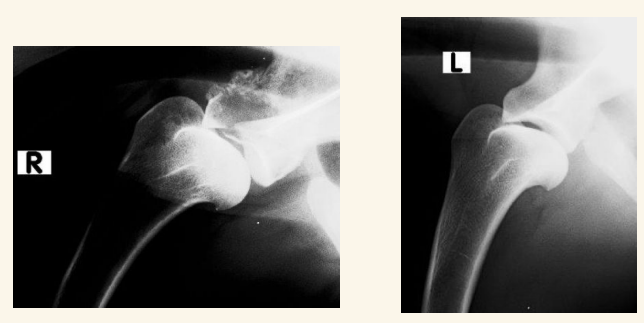

Hombro:

Luxaciones lo mas común (Puede ser congénita y traumática). Puede haber Osteocondritis disecante, Fracturas o EDA (Enfermedad Degenerativa Articular)